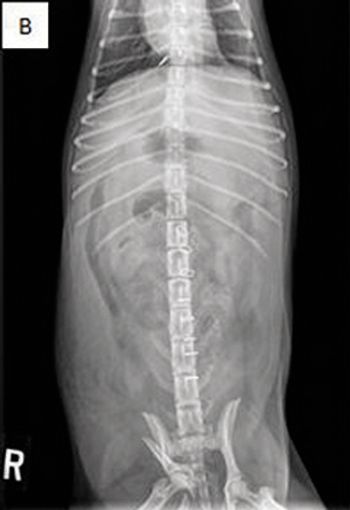

Examine the imaging results to help solve this pug's problem.